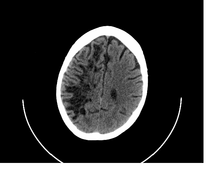

![]() A perivascular space as seen on CT | |

Perivascular spaces are extremely small and can usually only be seen on MRI images when dilated. While many normal brains will show a few dilated spaces, an increase in these has been shown to correlate with the incidence of several neurodegenerative diseases, making the spaces a popular topic of research.[1]

Perivascular spaces are distinguished on an MRI by several key features. The spaces appear as distinct round or oval entities with a signal intensity visually equivalent to that of cerebrospinal fluid in the subarachnoid space.[4][7][8] In addition, a perivascular space has no mass effect and is located along the blood vessel around which it forms.[7]